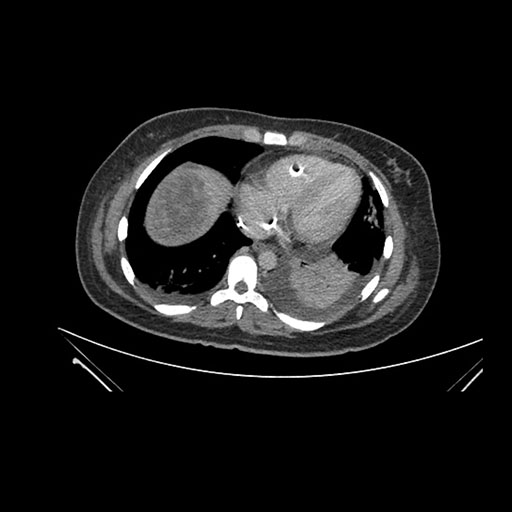

Axial Arterial

Axial Venous